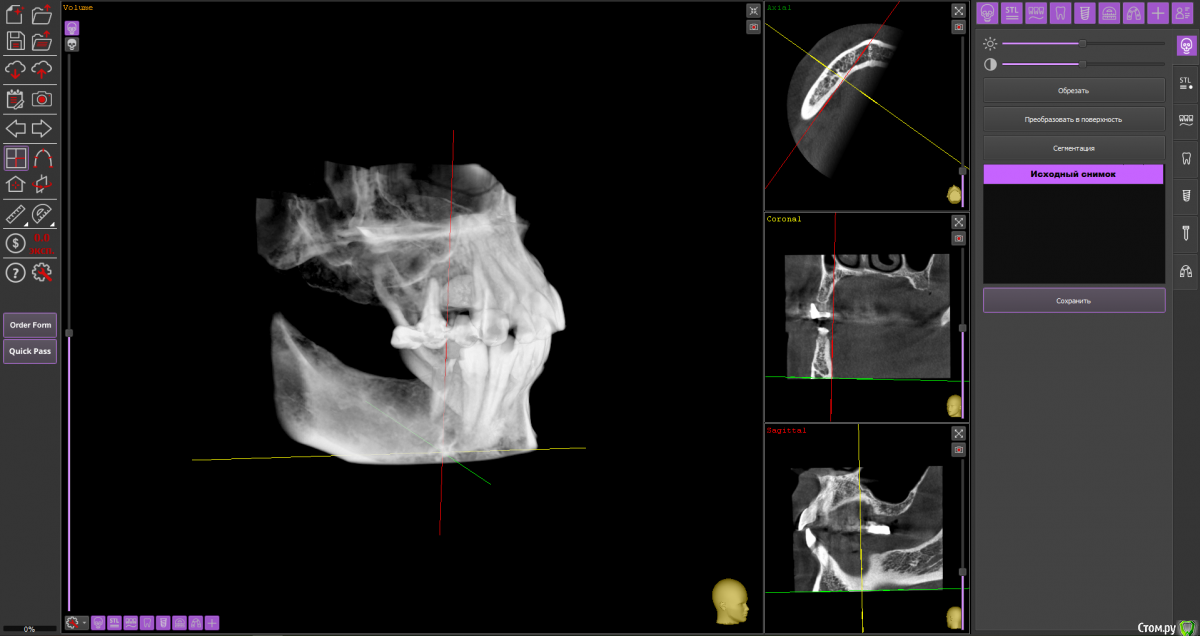

almaz7888 Опубликовано 11 февраля, 2021 Поделиться Опубликовано 11 февраля, 2021 (изменено) Доброе утро коллеги! Подниму тему. Данной пациентке планируется имплантация для замещения концевых дефектов на нижней челюсти. Зуб 3.5 думал удалить во время операции. Образование в области 3.5 это просто склероз кости? В области ментального отверстия справа также имеется какой-то очаг но меньших размеров. Изменено 11 февраля, 2021 пользователем almaz7888 Ссылка на комментарий